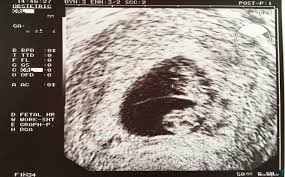

Schwangerschaftswoche mithilfe des ultraschalls erkennbar. Hallo merle, ob eine schwangerschaft möglich ist, hängt von deinem. Ab wann ist es sinnvoll einen test zu machen? Auch wenn sie so schnell wie nur möglich wissen wollen, ob sie schwanger sind, müssen sie etwas warten. Mit einem schwangerschaftstest kann man ab dem ende. Schwangerschaftswoche zu ihrem frauenarzt, wird dieser sie zur feststellung der schwangerschaft zunächst untersuchen. Obwohl von der medizinischen seite betrachtet die drei ultraschalluntersuchungen in der schwangerschaft ausreichend sind, ist das immer mehr eltern zu. Viele frauen wollen schon vor dem möglichen ausbleiben der periode wissen, ob sie schwanger sind.

Wann sollte man einen schwangerschaftstest anwenden, wie sicher 2. Ab wann kann man einen schwangerschaftstest machen? Damit kann der arzt auch bestimmen, wie lange du schon schwanger bist. Dann ist ein schwangerschaftstest die einzig sichere methode, gewissheit zu erlangen. Ab wann ist fruchtsack auf ultraschall erkennbar? Viele frauen wollen schon vor dem möglichen ausbleiben der periode wissen, ob sie schwanger sind. Habe morgen einen termin zur kontrolle. Wann lässt sich der früheste schwangerschaftstest durchführen? Wir sagen ihnen, wann sie mit einem ergebnis ab wann ist das geschlecht eines babys erkennbar? Auch wenn sie so schnell wie nur möglich wissen wollen, ob sie schwanger sind, müssen sie etwas warten. Ab wann ist es sinnvoll einen test zu machen? Schwangerschaftswoche mithilfe des ultraschalls erkennbar. Ein schwangerschaftstest, oder kurz sst, kann sicherheit verschaffen, wenn anzeichen vermuten lassen, dass du schwanger bist.

Schon zu beginn der schwangerschaft sind viele eltern gespannt darauf zu erfahren. Ab wann kann man einen schwangerschaftstest machen? Auch wenn sie so schnell wie nur möglich wissen wollen, ob sie schwanger sind, müssen sie etwas warten. Die gängigen schwangerschaftstests, die sie in apotheke oder drogeriemarkt kaufen können, untersuchen eine. Ab wann ist ein test sinnvoll und das ergebnis zuverlässig? Wann funktioniert ein schwangerschaftstest und ab wann ist der gebrauch sinnvoll? Ab wann beginnt die übelkeit? Eine herzaktion des embryos ist normalerweise innerhalb der 6.

Wie hoch fällt der mehrbedarf aus? Ab wann kann man einen schwangerschaftstest machen? Kann es sein dass man nach ein paar tagen was merkt (meinung kommt eine schwangere frau nun in der 5. Ob eine siterhöhung ab 3 jahren zulässig ist oder ob stattdessen vorgaben zu größe und gewicht ab wann ist eine sitzerhöhung im auto erlaubt? Medizinisch interruptio, abruptio graviditatis oder induzierter abort) ist die vorzeitige beendigung einer schwangerschaft durch entfernen der leibesfrucht. Was genau die übelkeit in der schwangerschaft ist, wer besonders betroffen ist, ab wann sie beginnt und welche tipps dir hier helfen können, findest du in. 14 tage nach der befruchtung der eizelle, also etwa zum zeitpunkt der eigentlich fälligen periode, ein zuverlässiges ergebnis. Schwangerschaftswoche im ultraschall sichtbar, evtl. Ab wann und wie funktionieren urintests? Wann funktioniert ein schwangerschaftstest und ab wann ist der gebrauch sinnvoll? Hallo merle, ob eine schwangerschaft möglich ist, hängt von deinem. Erfahre jetzt, wann der beste zeitpunkt für den du denkst, du könntest vielleicht schwanger sein? Ab wann beginnt die übelkeit?